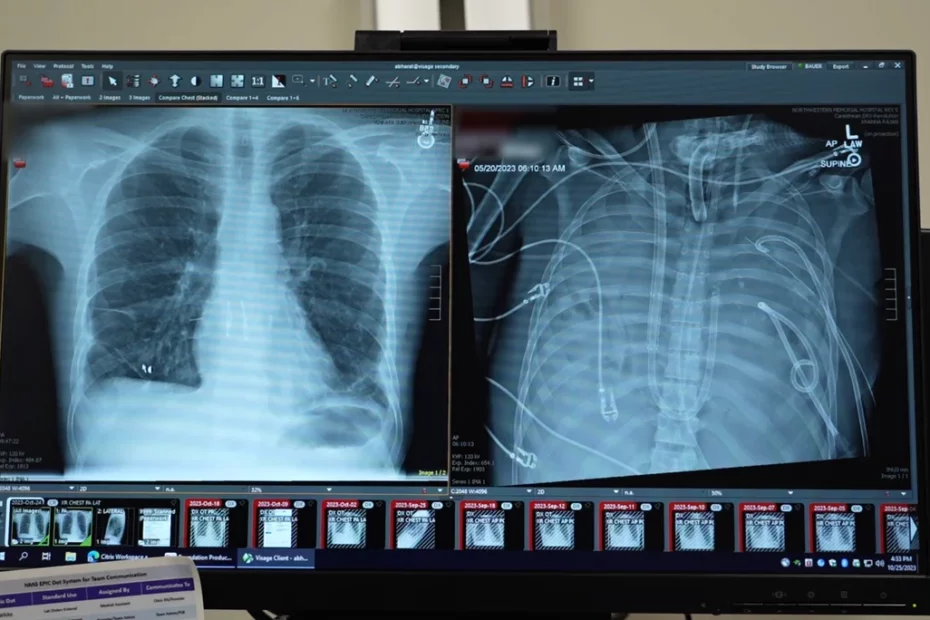

Cazul datează din 2023 și a fost coordonat de chirurgul toracic Ankit Bharat. Pacientul, internat cu gripă, dezvoltase o infecție secundară cu Pseudomonas, una dintre cele mai temute bacterii din spitale. Plămânii i se umpluseră cu lichid și puroi, rinichii începeau să cedeze, iar inima abia mai funcționa.

Bărbatul fusese conectat la ECMO (oxigenare extracorporală), un sistem de susținere a respirației, dar această metodă nu poate funcționa în absența plămânilor. În acel moment, pacientul a intrat în stop cardiac.

În fața acestui blocaj medical, echipa a decis să încerce ceva ce nu mai fusese aplicat până atunci în acest mod: să îi îndepărteze complet plămânii distruși și să construiască un sistem de „plămâni artificiali” care să preia temporar funcțiile acestora.

Dispozitivul creat de echipa lui Bharat a fost conceput ca o punte între partea dreaptă și cea stângă a inimii. Sistemul prelua sângele, îl oxigena și îl trimitea mai departe către restul corpului, exact așa cum ar fi făcut-o plămânii naturali.